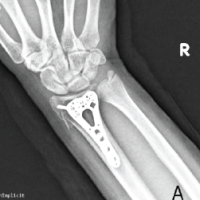

Both patients were positioned in the supine position, and a tourniquet was inflated to 250 mmHg at the start of the procedure. The surgical technique involved a closing wedge osteotomy of the radius combined with compression screw fixation to stabilize the lunate fracture. For osteotomy stabilization, a T-plate was applied to the distal radius: a palmar approach following Henry’s technique was used for Patient A, whereas a dorsal approach centered on the third ray was employed for Patient B. The lunate fracture was stabilized using a cannulated compression screw: A SpeedTip 2.2 mm Medartis screw (Fig. 7) for Patient A and an HCS 2.4 mm compression screw (Fig. 8) for Patient B.

Figure 7: Patient A – post surgery.

Figure 8: Patient B – post surgery.

The mean follow-up duration was 24 months (Patient A: 36 months and Patient B: 12 months). Bone consolidation of the radial osteotomy was achieved on average 3 months postoperatively for both patients, while consolidation of the lunate fracture occurred at 6 months for Patient A (Fig. 9) and at 7 months for Patient B (Fig. 10). Lunate fracture union and radial osteotomy union were assessed with CT.

Figure 9: Patient A – X-ray and computed tomography scan: radius/ lunate consolidation.

Figure 10: Patient B X-ray and computed tomography scan: radius/ lunate consolidation.

CT was chosen because it is widely regarded as more reliable than radiographs for assessing carpal bone union and arthrodesis/osteotomy healing, and is appropriate when the clinical course is favorable. Routine post-operative perfusion studies were not pursued because the clinical evolution was satisfactory, and structural union had been demonstrated on CT.

The distal radius plate was removed due to discomfort at 13 months for Patient A and at 3 months for Patient B.